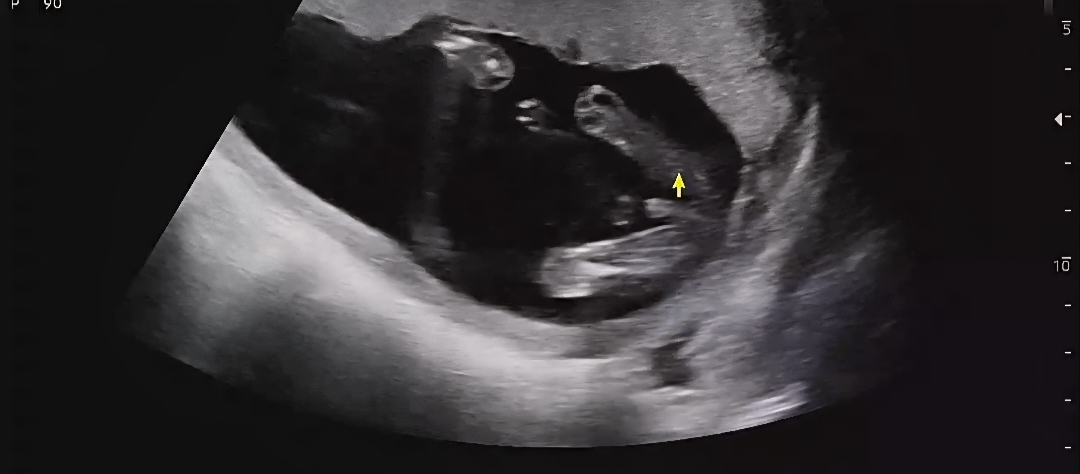

ㅎㅎ 아들확정이네용